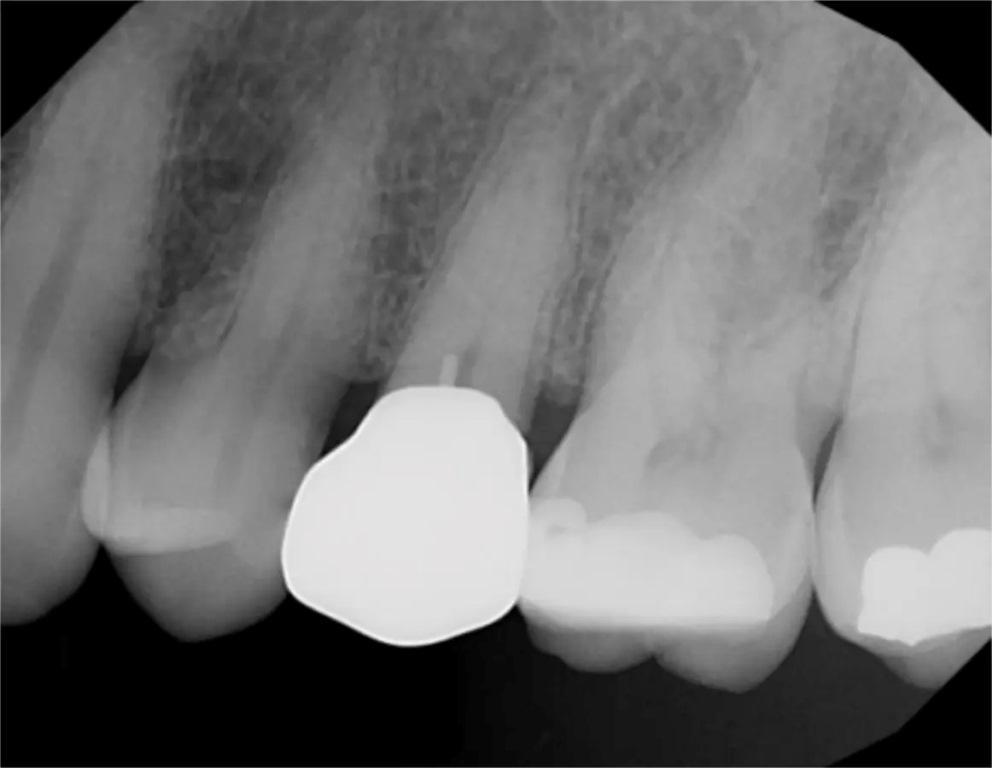

57-летний пациент обратился с жалобами на повышенную чувствительность к температуре в левом квадранте верхней челюсти. Был сделан рентгеновский снимок (фото 2), на котором был отмечен глубокий кариес на втором премоляре с возможным вовлечением пульпы. Периапикальная патология рентгенологически не была отмечена. Чтобы убедиться в жизнеспособности пульпы зуб подвергли испытанию холодом (фриз-тест). При проведении фриз-теста была отмечена слабая реакция, которая немедленно прошла, когда холод был удален с зуба, что указывало на то, что зуб был жизненно важным. Пациенту сообщили, что может потребоваться эндодонтическое лечение, если в результате удаления кариеса произойдет значительное обнажение пульпы или у зуба появятся симптомы после лечения. Если обнаруживается небольшое обнажение пульпы или в результате удаления кариеса дентин над пульпой становится тонким, перед установкой культевой вкладки следует провести лазерную обработку, чтобы стерилизовать область и избежать развития пульпита. Для этого зуба планировалось установить культевую вкладку и полную коронку. Пациент принял рекомендации по лечению.

Фото 2: Периапикальная рентгенограмма зуба №25, на которой виден кариес в непосредственной близости от пульпарной ткани.